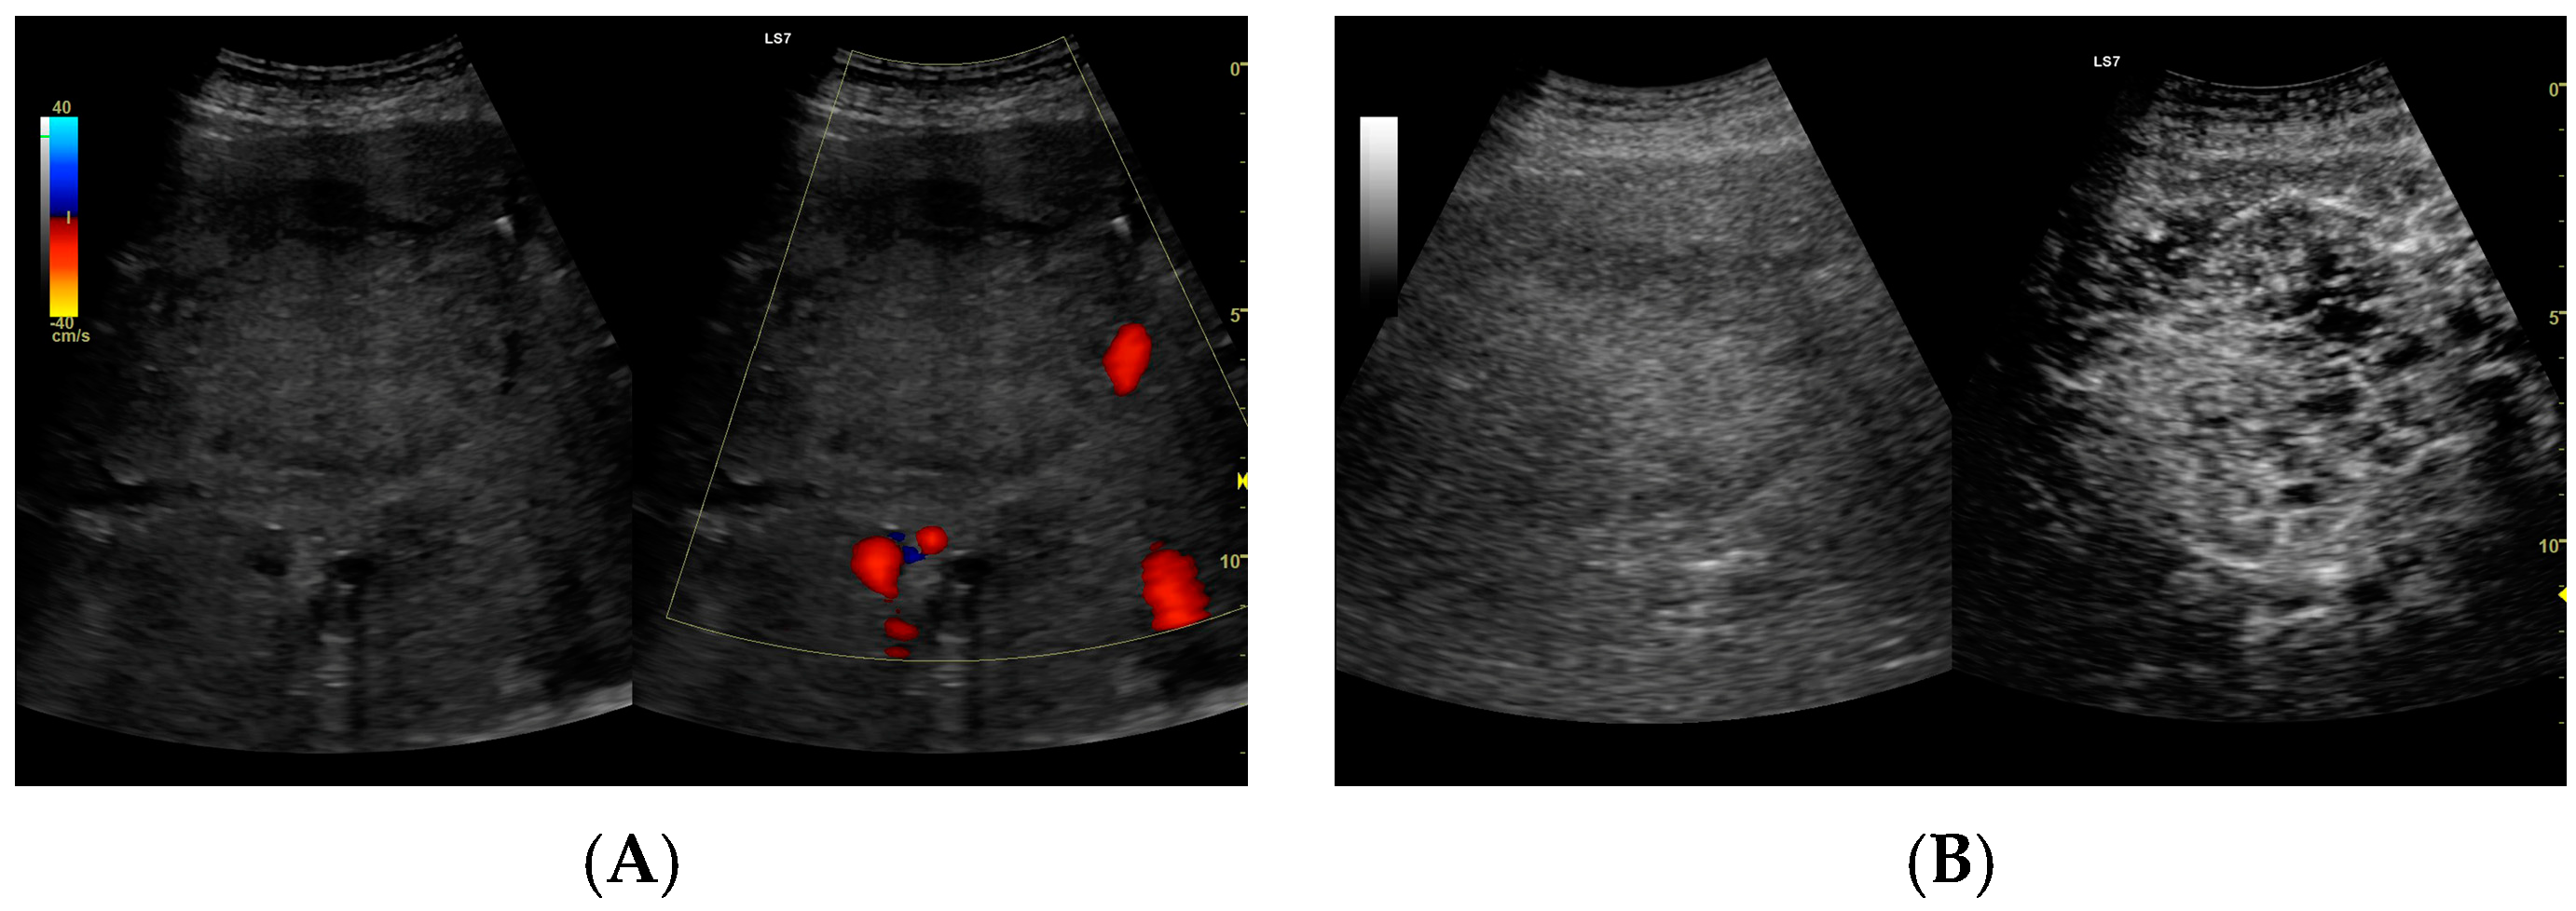

CEUS was conducted in alignment with the 2020 guidelines for liver applications [5]. The imaging utilized a GE Logiq 7 system (GE Healthcare, Milwaukee, WI, USA) equipped with a 4C convex probe. Initial B-mode scans of the liver were performed to document the size, location, and number of lesions. Following this, color Doppler imaging was conducted. The next step involved administering 2.4 mL of SonoVue contrast agent via the medial cubital vein, typically adequate for accurate diagnosis. Additional contrast was injected as required, especially in cases involving multiple lesions. The CEUS protocol employed a low mechanical index (<0.1) to preserve the microbubbles of the contrast agent [6,7]. Three primary acquisition phases were observed: the arterial phase (10–45 s), the early venous phase (45–120 s), and the late venous phase (120–180 s) [5]. After 120 s, no significant changes in the dynamic enhancement profile were noted. Lesions located deep beneath the diaphragm necessitated deep inhalation and breath-holding by patients, complicating the acquisition in certain cases. Extended acquisition was only pursued for ambiguous cases. The enhancements of the HA walls and the pus were assessed in comparison to the liver parenchyma as depicted in Figure 1. B-mode and CEUS images were independently evaluated by two radiologists to ascertain the size of the lesion and its liquid content.

In the post–contrast CEUS assessment, regions of interest (ROIs) were designated within the lesion (colored red for pus and blue for the abscess capsule) and in the liver parenchyma (colored yellow). We tracked enhancement curves for 2–3 min, capturing data in 20–30 s intervals. Any data distorted by movement artifacts, which displaced the ROIs, were excluded from the analysis.